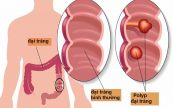

Đa polyp gia đình (FAP) là một bệnh di truyền hiếm gặp. Bệnh gây ra những khối u phát triển trên bề mặt lớp biểu mô đại tràng (còn gọi là polyp). Vậy triệu chứng và nguyên nhân của bệnh lý này là gì? Làm thế nào để điều trị và phòng ngừa bệnh hiệu quả? Tham khảo bài viết dưới đây để hiểu rõ hơn nhé!